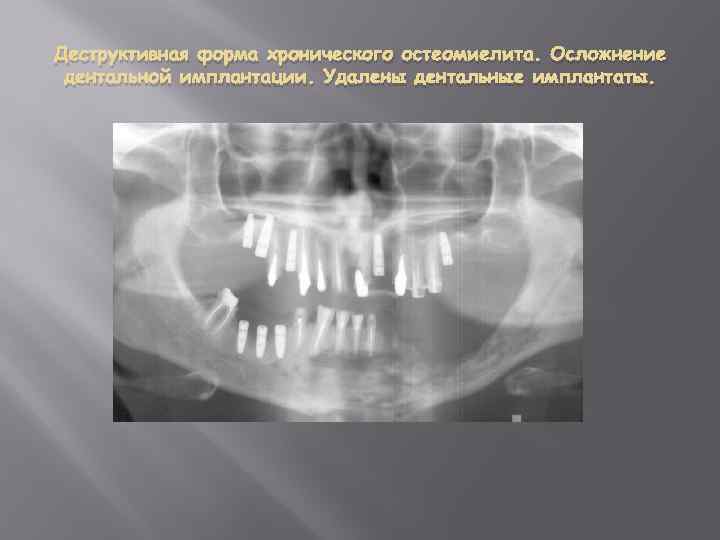

Деструктивная форма хронического остеомиелита. Осложнение дентальной имплантации.

Деструктивная форма хронического остеомиелита. Осложнение дентальной имплантации. Удалены дентальные имплантаты.